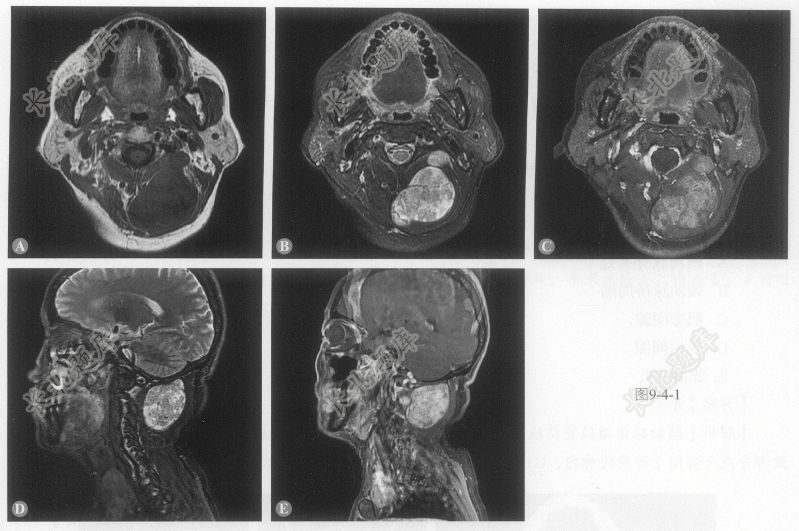

[材料题] 患者女性,58岁,8年前无诱因出现左颈部疼痛伴肿物,未特殊治疗,后肿物逐渐长大,拟手术切除。MRI平扫及增强如图9-4-1:

单项选择题1.病变位于:

单项选择题2.病变影像学特点:

单项选择题3.病变定性:

单项选择题4.可能的诊断: